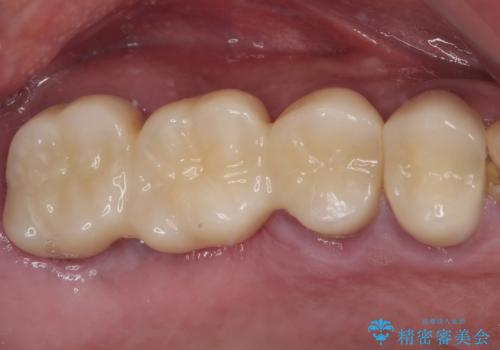

割れてしまった奥歯 抜歯即時埋入インプラントによる短期間治療